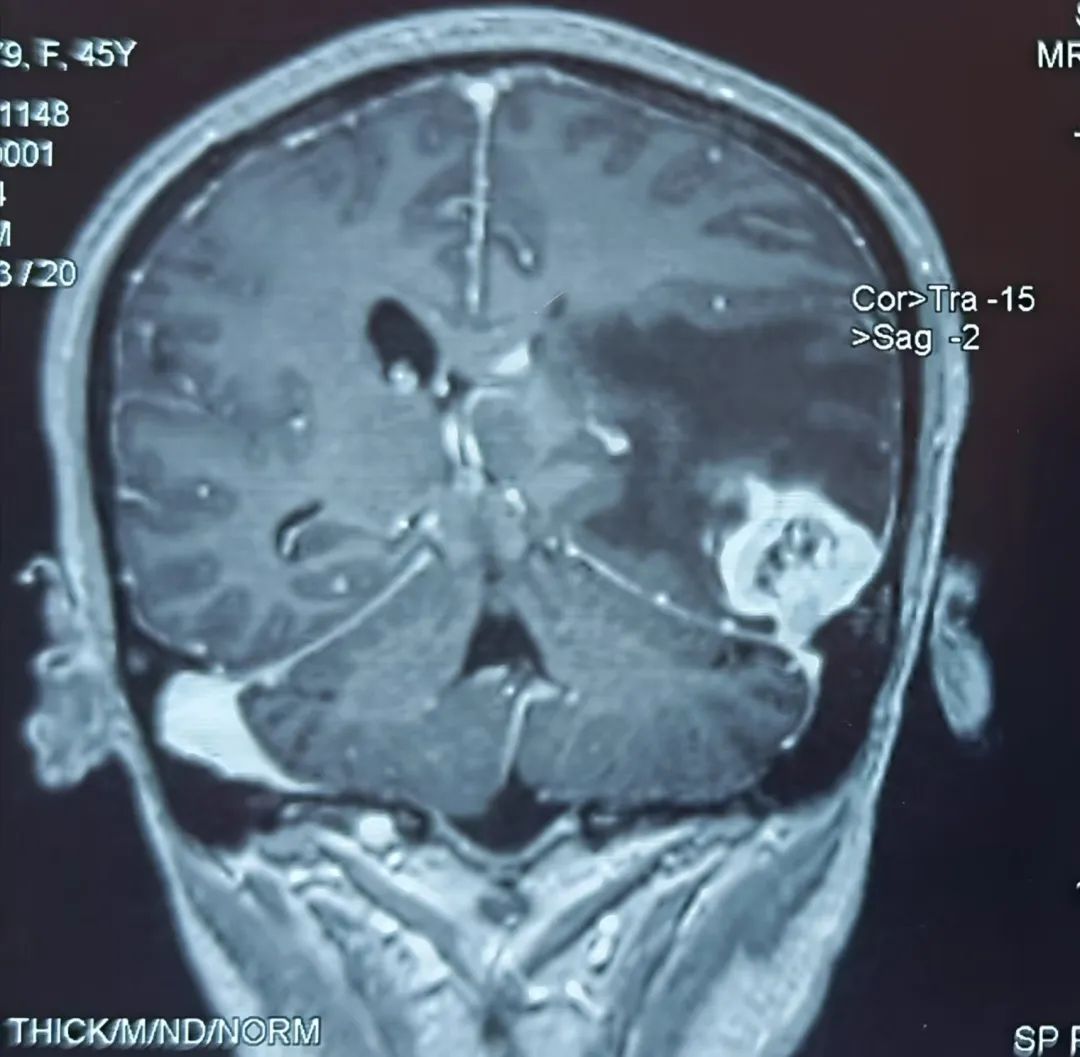

患者43歲,腎腫瘤術(shù)后一個(gè)半月開(kāi)始出現(xiàn)頭痛難忍,伴有惡心、嘔吐、言語(yǔ)不流利,每天靠止痛藥緩解頭痛,到醫(yī)院行頭部核磁檢查提示左顳葉占位,考慮腦轉(zhuǎn)移瘤可能性大。為進(jìn)一步診治,在朋友的介紹推薦下,患者來(lái)到我院神經(jīng)外科找到桑文淵主任。桑主任詳細(xì)詢(xún)問(wèn)病史,仔細(xì)閱片后,初步診斷患者為腦轉(zhuǎn)移瘤。

患者術(shù)前核磁影像

得知再患腫瘤,患者及家屬情緒極為低落。桑文淵主任給予耐心安撫溝通,表示頭痛、惡心、嘔吐、言語(yǔ)不流利這些癥狀都是腦轉(zhuǎn)移瘤顱內(nèi)壓增高造成的。通常腦轉(zhuǎn)移瘤周?chē)[嚴(yán)重,顱腔空間狹小,耐受力有限,如不積極手術(shù),隨著腫瘤不斷增大,水腫加重,隨時(shí)會(huì)有生命危險(xiǎn)?;颊吣X轉(zhuǎn)移瘤為單發(fā),具備手術(shù)指征,需要盡快手術(shù)切除,為后續(xù)綜合治療贏得時(shí)間?;颊呒覍倭私獠∏楹螅e極要求手術(shù)切除腦腫瘤。